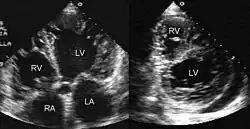

Als (isolierte) Non-Compaction-Kardiomyopathie (NCCM, synonym Isolated Noncompaction of Ventricular Myocardium, INVM) wird eine seltene, genetisch bedingte Störung der Herzmuskel-Verdichtung (primäre Kardiomyopathie) während der embryonalen Organentwicklung bezeichnet, die 1984 erstmals beschrieben wurde.[1] Das klinische Krankheitsbild umfasst Zeichen der Herzinsuffizienz, Herzrhythmusstörungen sowie Komplikationen durch Thrombemboliebildung. Die Diagnose erfolgt mittels Echokardiografie oder Magnetresonanztomographie. Die Behandlung ist symptomatisch, eine ursächliche Therapie ist nicht möglich.

Die Diagnostik der Wahl ist die Herzultraschalluntersuchung (Echokardiografie). Es wurden diagnostische Kriterien der NCCM definiert. Eine Alternative stellt das Kardio-MRT (Magnetresonanztomographie) dar. Als cut-off gilt ein Verhältnis >2,3 zwischen nicht-kompaktem Myokard und kompakten Myokard. Die Laborparameter der Herzdiagnostik sind im Allgemeinen normal. Wegen einer möglichen familiären Häufung werden Screening-Untersuchungen der Familien empfohlen.